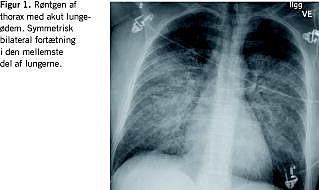

En 49-årig rask kvinde blev kl. 12.30 indbragt til skadestuen efter fald fra en hest. Angiveligt havde hesten stejlet, hvorefter hun faldt af, og hesten væltede ned over hendes abdomen og bækken. Ved ankomsten klagede patienten over smerter i højre hofte og smerter i nedre venstre kvadrant af abdomen. Røntgen af bækkenet viste normale forhold. Herefter blev computertomografi (CT) af abdomen gennemført. Kl. 13.38 blev der indgivet kontrast (iomeprol, 150 ml, 4 ml/s), og i tilslutning til undersøgelsen klagede patienten over en klemmende fornemmelse i halsen. Umiddelbart måltes blodtrykket til 135/70 mmHg, og symptomerne fortog sig. CT'en viste ingen tegn på traumatiske læsioner og helt normale forhold i de medskannede basale lungeafsnit. Patienten blev returneret til skadestuen til fortsat observation, hvor hun ca. 35 minutter efter kontrastindgift blev akut påvirket med blodtryksfald til 88/60 mmHg, bleghed og dyspnø. Iltbehandling på maske indledtes, men trods dette var saturationen faldende, hvorfor patienten blev intuberet. Umiddelbart inden intubationen havde en røntgenundersøgelse af thorax vist begyndende lungeødem. På mistanke om allergisk reaktion blev der givet adrenalininhalation 0,5 mg/ml, 4 ml, clemastin 2 mg og hydrocortison 200 mg intravenøst (i.v.). Foranstående blev yderligere suppleret med methylprednisolon 80 mg, furosemid 80 mg i.v. En akut ekkokardiografi kl.15.45 viste uddrivningsfraktion på ca. 50%, ingen tegn på hjertekontusion og intet perikardieekssudat.

Kl. 20.15 blev patientens tilstand konfereret med nærmeste universitetshospital med henblik på ekstrakorporal cirkulation (ECMO). ECMO-holdet blev umiddelbart mobiliseret med efterfølgende ankomst til intensivafdelingen omkring kl. 22. På dette tidspunkt havde patienten umåleligt blodtryk, hvorfor der samtidig med klargøring til ECMO-behandling blev givet hjertemassage samt i.v. adrenalin. Røntgen af thorax optaget kort forinden viste betydelig stase og pleuraekssudater. På grund af hjertepumpesvigt blev behandlingen indstillet. Mors kl. 22.40.

Patofysiologien bag disse alvorlige anafylaktiske/anafylaktoide reaktioner er omdiskuteret. Ud over den klassiske immunglobulin E (IgE)-medierede type 1-reaktion har man i flere studier påvist, at fatale kontrastreaktioner medieres på anden vis. Kontraststoffer kan påvirke mastceller og basofile celler til histaminfrigørelse ved direkte påvirkning eller ved påvirkning via enten T-lymfocytter, komplementsystemet eller immunologiske mekanismer [2]. At der kan være tale om en anden mekanisme end en type 1-reaktion understøttes endvidere af, at der hos visse patienter, som har haft en kontrastrelateret allergisk reaktion, ikke er fundet IgE-antistoffer mod kontrast, og at den livstruende/anafylaktoide reaktion er opstået uden forudgående eksponering for kontraststof [5]. Hvad enten den fatale reaktion er anafylaktisk eller anafylaktoid, induceres vasodilatation, øget karpermeabilitet og brokospasme, hvilket medfører ensartet symptomatologi (Figur 1 ).